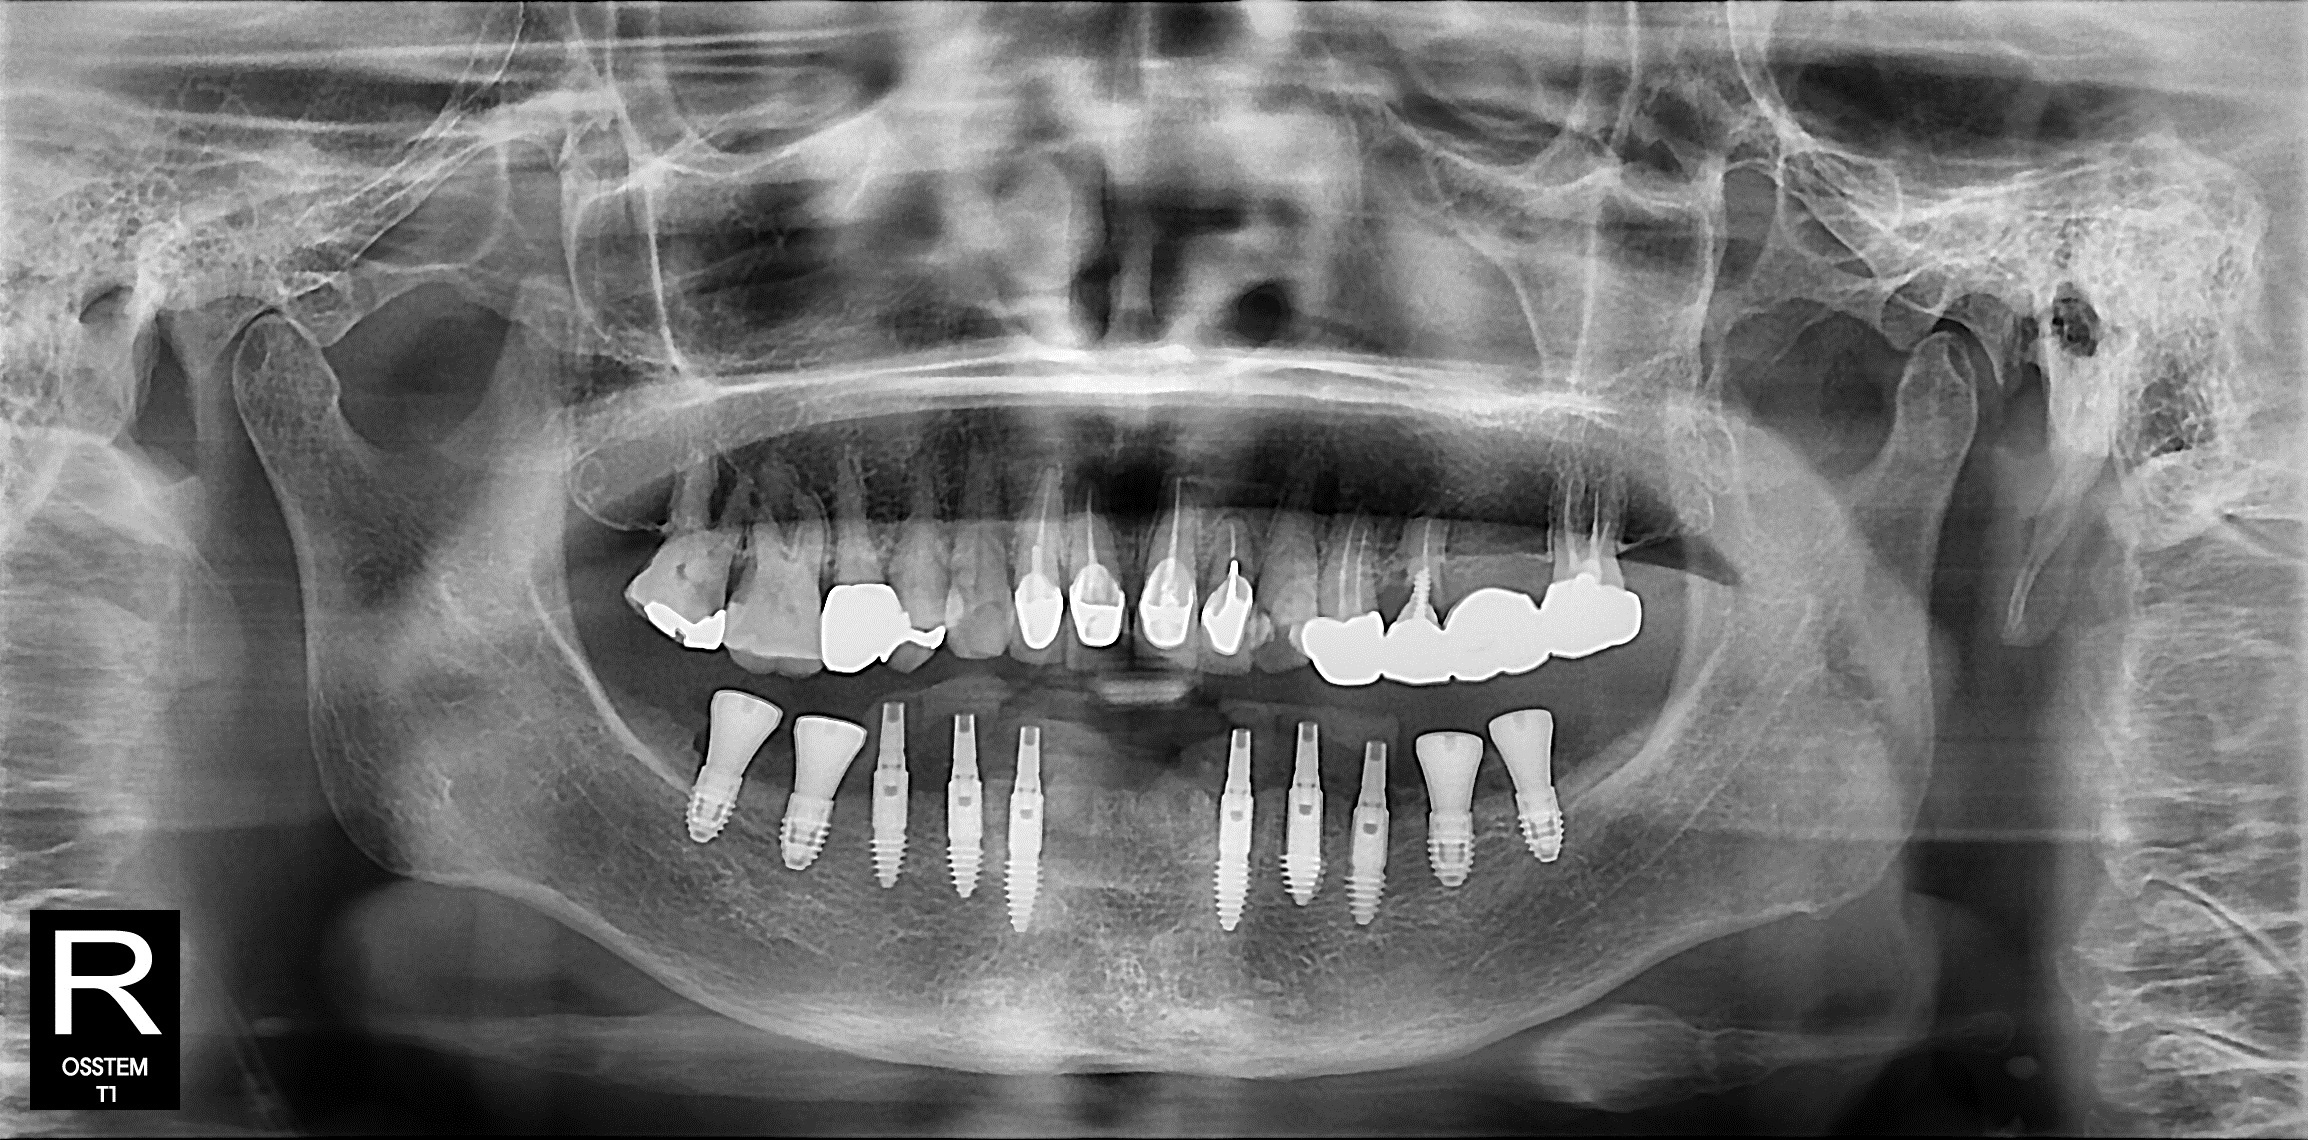

이번 케이스에서도

그 기저골을 하나하나 찾아내

픽스쳐가 최대한

‘튼튼한 곳’을 잡을 수 있도록

각도를 미세하게 조정하며 식립했습니다.

이런 작업은 말 그대로

“손기술 + 경험”의 영역입니다.

정석적인 해부학적 지식만으로는 불가능하고,

오랜 수술 경험이 있어야

가능한 부분입니다.